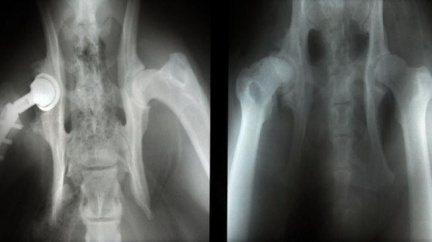

Artrózu mají v ČR dva miliony lidí, hlavní prevencí je pohyb

Artrózu mají dva miliony Češek a Čechů, postihuje každého pátého člověka nad 45 let a 60 procent lidí starších 65 let. I proto jsou reklamní preparáty na klouby oblíbeným vánočním dárkem pro seniory.